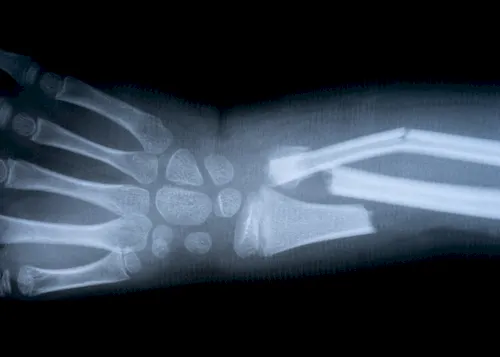

| ▸ | Röntgen Erkennung von Knochenbrüchen (zuverlässige Ergebnisse erst im späteren Krankheitsverlauf – neue, starke Rückenschmerzen; chronische Rückenschmerzen unbekannter Ursache; hohes Lebensalter; niedrige Knochendichte; mehrere, alte Brüche; Größenverlust von > 5 cm seit 25. Lebensjahr und > 2 cm bei Kontrolluntersuchungen) |

| ▸ | Computertomografie (CT), Magnetresonanztomografie (MRT) Erkennung von frischer oder verheilter Fraktur und genaue Auswertung der Frakturmorphologie |

Röntgenaufnahmen von verschiedenen Knochenbrüchen bei Osteoporose

Diese Diagnostikmethoden kombiniert sind von großer Bedeutung, um individuelle Risikoprofile zu erstellen und eine präzise Behandlung einzuleiten. Eine frühzeitige Untersuchung ermöglicht es Ihnen, gezielt Maßnahmen zu ergreifen und so die Stabilität Ihres Knochengerüsts langfristig zu sichern.